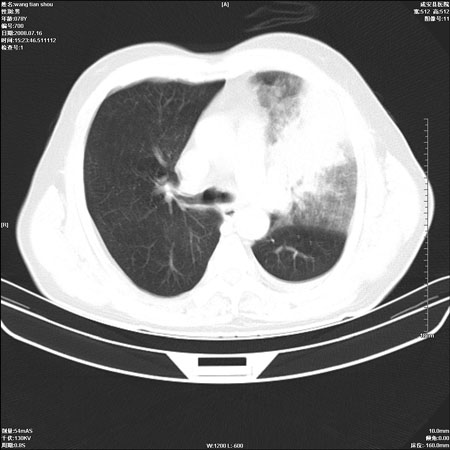

以下是引用qingjing在2008-7-16 19:55:00的发言:[br]1、左上肺不张并堵塞性炎症,建议支气管镜详查;[br]2、左侧胸腔少量积液。

以下是引用zsl6918在2008-7-17 8:09:00的发言:[br]肺炎胸膜炎可能性大,建议抗炎治疗后复查

以下是引用wzr在2008-7-16 20:26:00的发言:[br]左肺肺不张伴阻塞性肺炎!另:左侧胸腔少量积液。建议纤支镜检查!